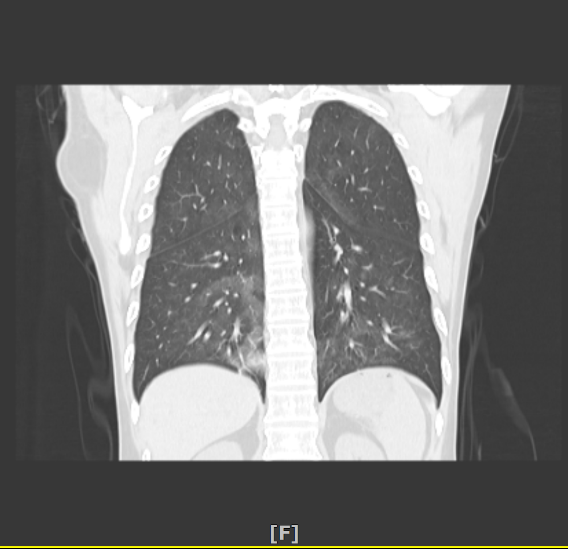

2020年10月27日因“淋巴瘤化疗后发热5天”来我院治疗。入院时血常规正常,CRP51.75mg/L,PCT阴性,血气未见明显异常,血清(1-3)-β-D-萄聚糖阳性(G试验)549.14pg/ml(≥100pg/ml阳性),GM试验阴性,LDH 537.3U/L、CMV和EB病毒定量阴性;胸片示肺间质改变明显,胸部CT示两肺弥漫磨玻璃样模糊影,考虑PCP可能大。

PCP影像学随着病程进展呈现动态变化,疾病不同时期表现可明显不同,典型表现为双肺弥漫性或局限性磨玻璃样影像,星云雾状、树枝挂霜样改变,呈非对称性、非均匀性随机分布;慢性或复发病例可引起间质结构和小叶间隔的增厚。